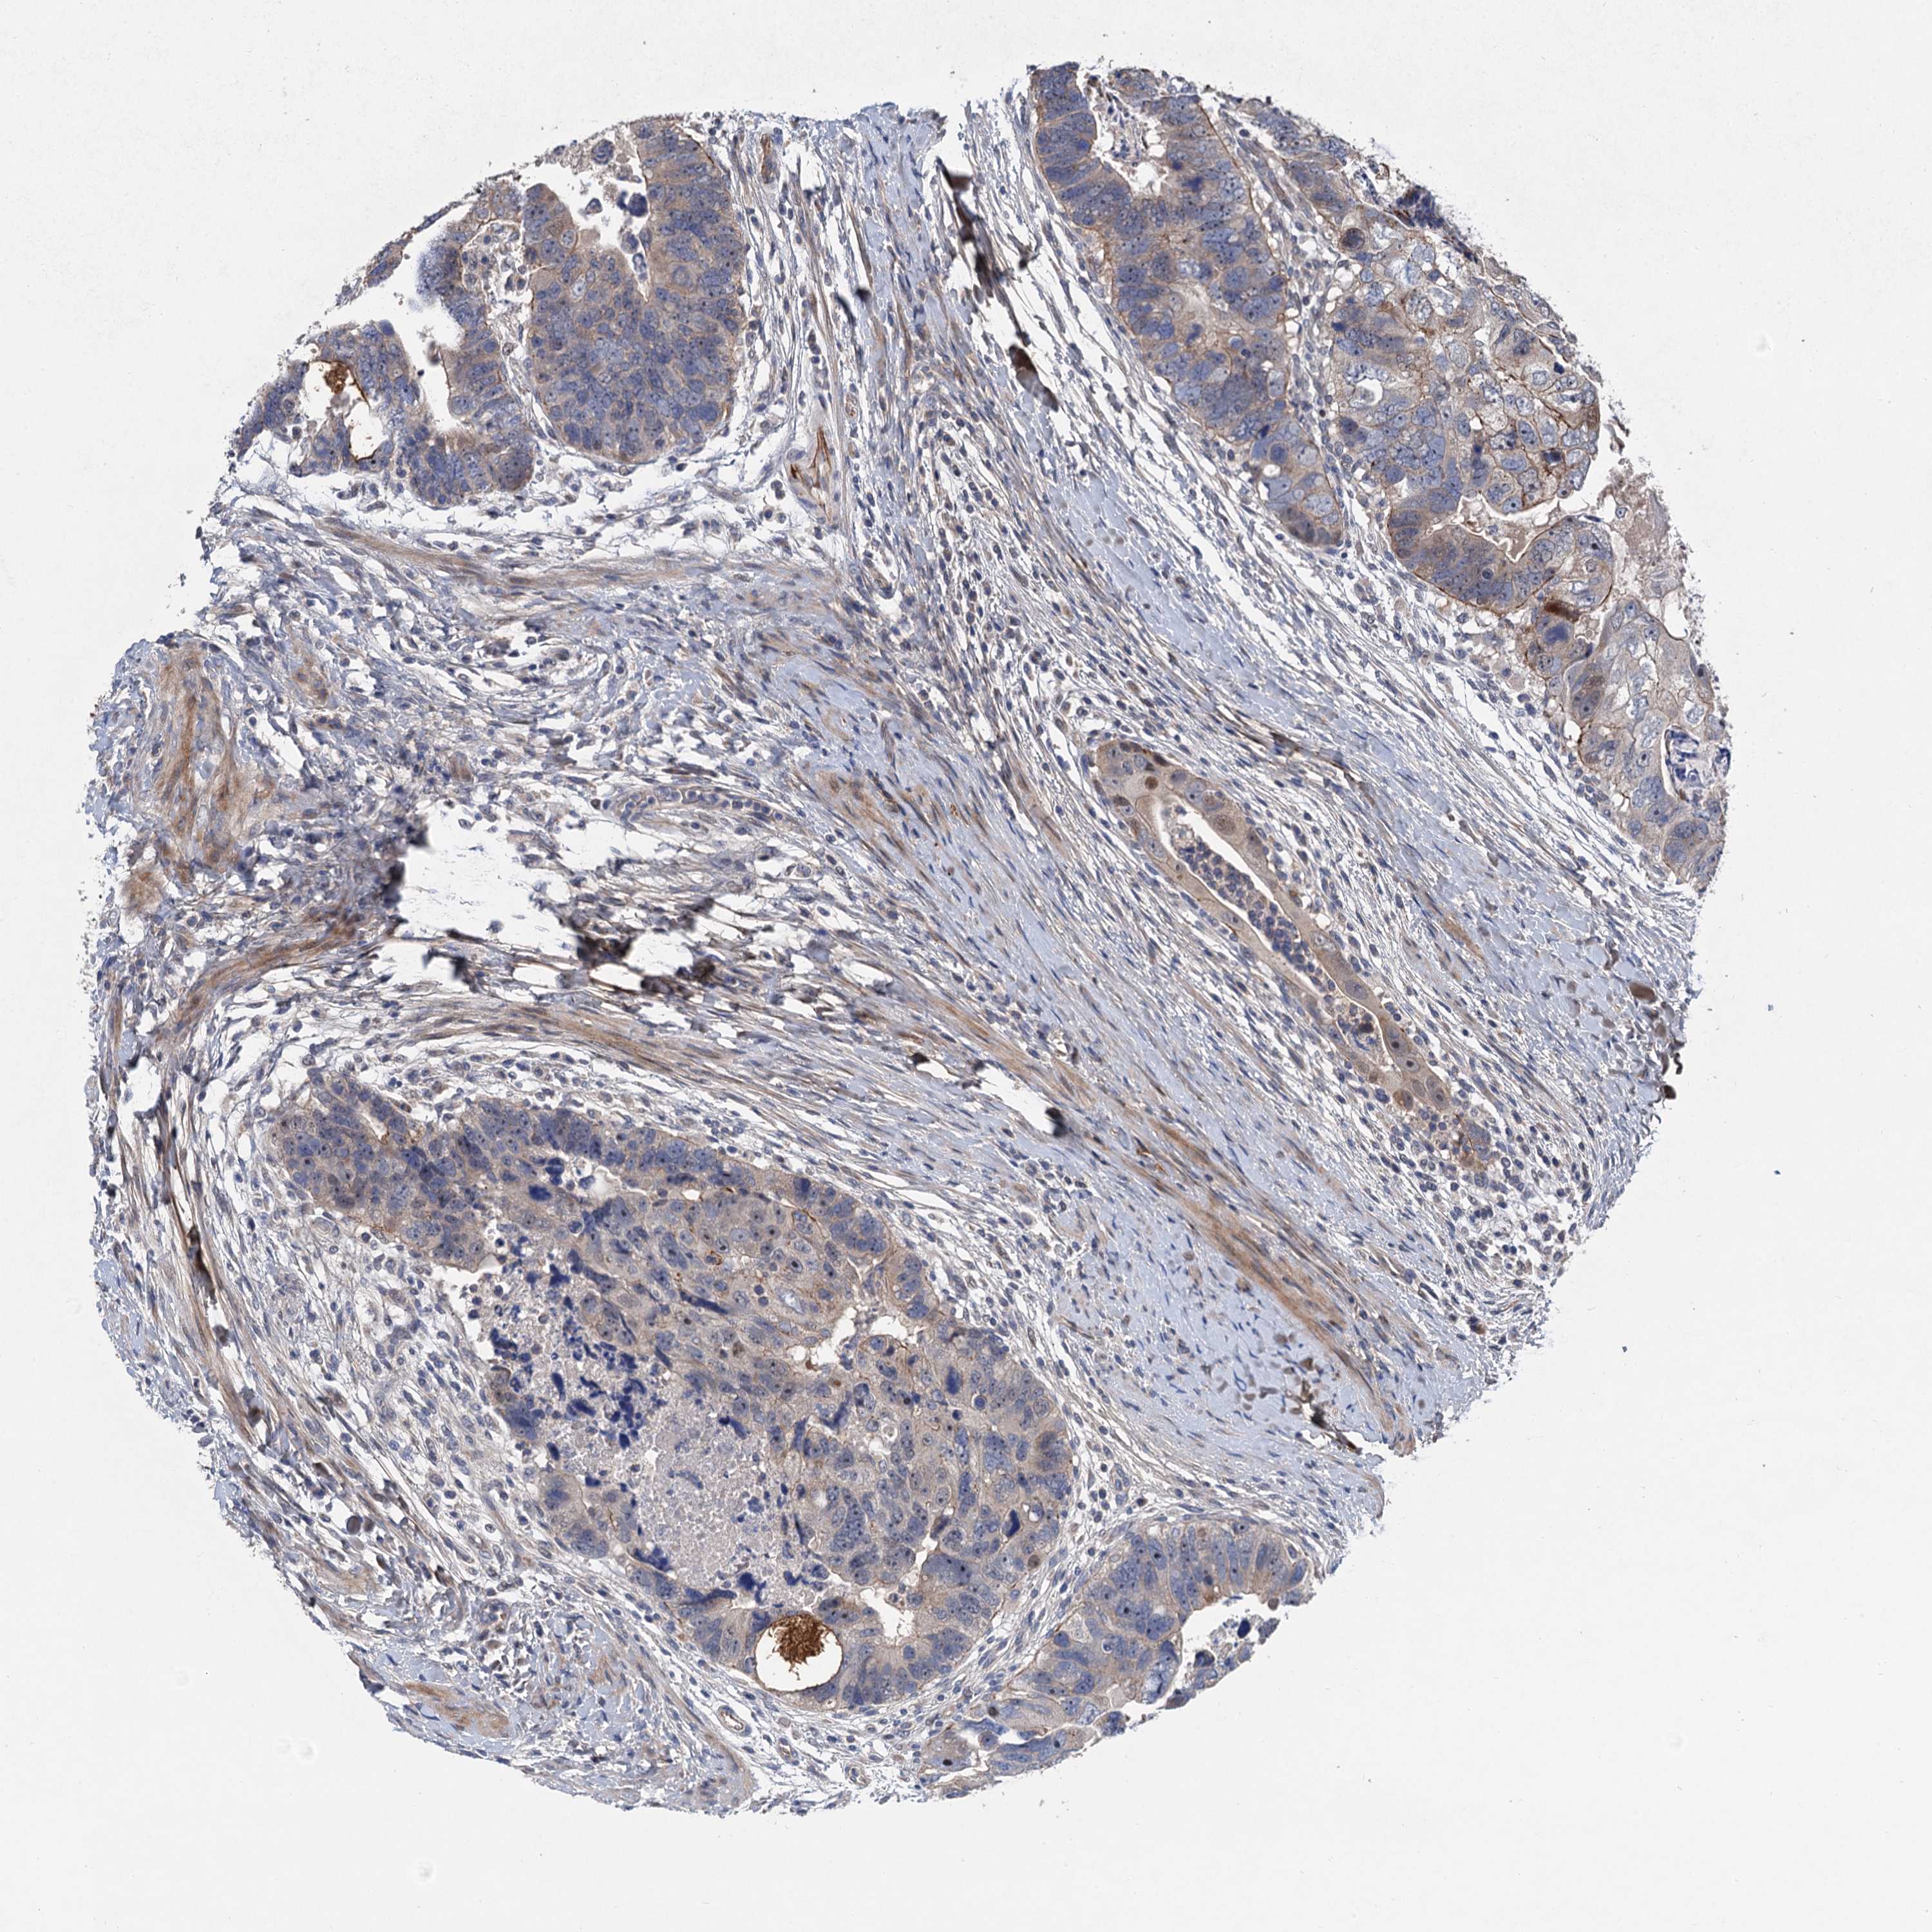

CANCER COLORECTAL CANCER Show tissue menu

Colorectal cancer

Human cancer

Colon adenocarcinoma